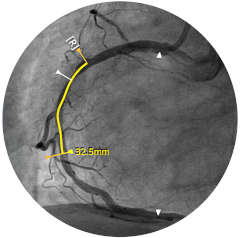

Abbildung 1

Abbildung 2

Abbildung 3

Abbildung 4